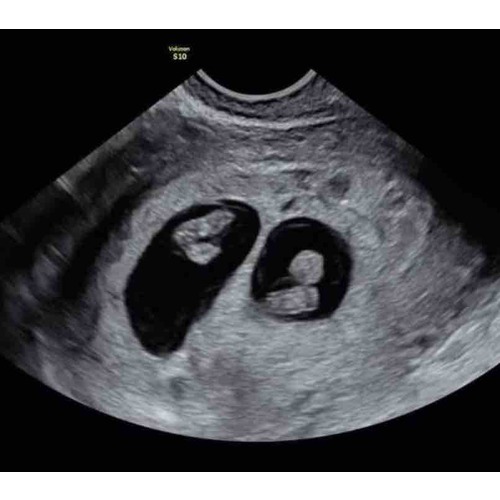

I am so sorry but You are not pregnant. You say your 15 weeks but it is impossible, Hereby an ultrasound of 7 weeks and twins. I am so sorry for You,.. i know it is not the awnser You want to here but this is the reality.